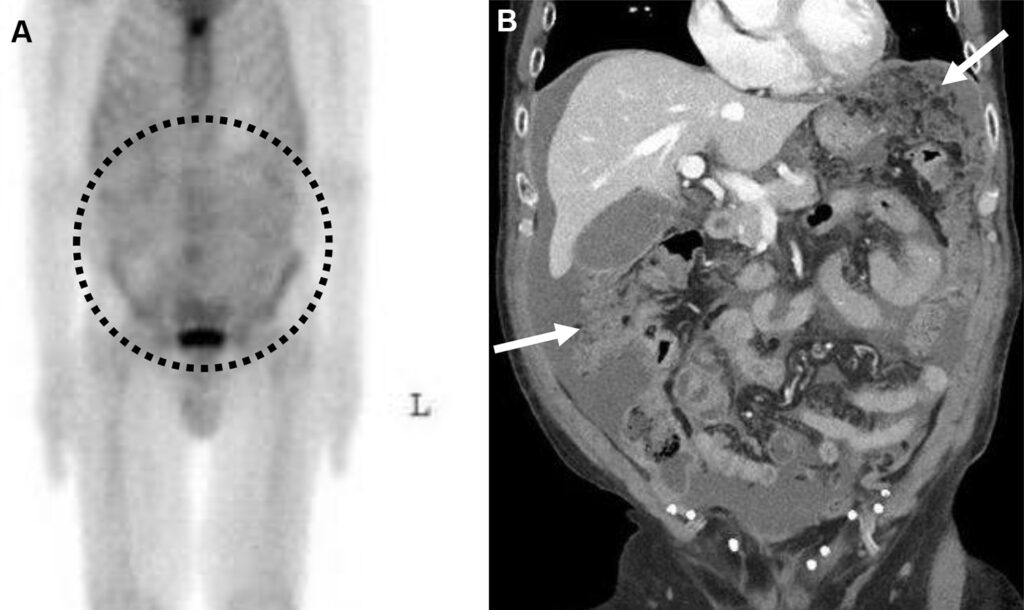

Donna di 47 anni con carcinoma neuroendocrino polmonare in stadiazione pre-trattamento.

L’imaging funzionale ha rilevato una chiara ipercaptazione patologica alla vertebra L5, caratterizzata da un elevato valore quantitativo (SUVmax = 45.41). Tuttavia, l’imaging morfologico (TC) iniziale era completamente negativo, non mostrando alterazioni strutturali dell’osso (C).

A distanza di tempo, l’esame TC di controllo ha documentato l’insorgenza di reazione osteoblastica (sclerosi) esattamente nello stesso punto segnalato dalla SPECT/TC mesi prima (E).

Questo caso “vero positivo” dimostra l’eccellente sensibilità dell’imaging scintigrafico (e in particolare della SPECT/TC quantitativa) nell’identificare micrometastasi o lesioni ossee in fase estremamente precoce, con largo anticipo rispetto alla comparsa dei segni morfologici visibili alla radiologia tradizionale.

Uomo di 70 anni con carcinoma adenosquamoso polmonare in stadiazione pre-trattamento.

L’imaging scintigrafico e SPECT/TC ha rilevato un’ipercaptazione focale a livello dell’osso iliaco destro (SUVmax = 15.60), corrispondente ad un’area di sclerosi ossea alla TC di natura non univoca (2,6 x 1,6 cm, densità media di 650 HU).

Nonostante la malattia di base sia andata in progressione sistemica (comparsa di metastasi al fegato e alla vertebra L1), la lesione iliaca è rimasta morfologicamente e densitometricamente stabile ad oltre un anno di distanza (dimensioni invariate, densità di 648 HU).

Questo caso “vero negativo” illustra un tipico pitfall diagnostico. La stabilità dimensionale e densitometrica (espressa in Unità Hounsfield) nel tempo conferma che l’area osteosclerotica ipercaptante non era una metastasi, ma una lesione ossea benigna (probabilmente un’isola ossea o enostosi).